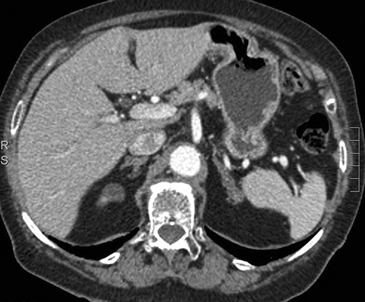

c) Comportamiento de la lesión con el uso de medio de contraste endovenoso

Luego de la administración de contraste endovenoso los adenomas aumentan su densidad debido a que son vascularizados, lo que se puede objetivar midiendo directamente el valor de atenuación en UH, pero tiene una particularidad en que, el lavado de contraste es más rápido que el de las lesiones no adenomas incluidas las malignas. Las lesiones malignas tienen una red capilar de mayor densidad, con flujo más lento, y los capilares de neoformación son más porosos, por lo que el medio de contraste difunde con facilidad al espacio extravascular. Así, el medio contraste tiende a acumularse en el tejido y a lavarse lentamente, a diferencia de lesiones benignas en que el lavado contraste es rápido porque al estar la red capilar intacta el medio de contraste se queda intravascular. Dado que el valor de atenuación absoluto depende de la dosis de contraste, flujo y gasto cardiaco entre otros factores, se ha considerado de mayor utilidad realizar una comparación relativa porcentual, comparando la densidad de la lesión en la fase contrastada con la densidad de la lesión en fase tardía y así estimar el lavado de la lesión. Muchos exámenes de TAC abdominal en que no se sospecha una lesión suprarrenal, se realizan con medio de contaste ev sin contar con una fase no contrastada, por lo que no se dispone del valor de atenuación original de la lesión. En estos casos si se detecta una lesión suprarrenal incidental, se obtiene una fase tardía a los 15 minutos después de la administración del contraste ev para poder estimar el porcentaje de lavado en la lesión. Si se dispone del valor de atenuación en fase no contrastada se puede calcular el porcentaje de lavado absoluto y si solo se dispone de fase contrastada se calcula el porcentaje de lavado relativo (Tabla 1).

Los valores más utilizados son un 40% de lavado relativo de en fase tardía realizada a los 15 minutos y un lavado absoluto de 60%. De este modo cualquier lesión que muestre un lavado relativo mayor al 40% o absoluto mayor al 60% es consistente con un adenoma, con una sensibilidad y especificidad cercana al 100% (Figura 14 a, b y c). Dado la rapidez con que se obtiene un TAC de abdomen en la actualidad, algunos trabajos han recomendado utilizar cortes tardíos realizados a los 10 minutos, con el fin de optimizar el tiempo de examen, y utilizar un valor relativo de corte más conservador del 50%9.

C Figura 14. Tomografía computada de un adenoma suprarrenal izquierdo típico. Se ha colocado un circulo que representa la región de interés en la lesión de la glándula suprarrenal izquierda, obteniendo una medición promedio (Avg) expresada en unidades Hounsfield (UH). En fase precontraste (a) su densidad es de 0 UH, (flecha), en fase protovenosa (b) alcanza una densidad de 59 UH (cabeza de flecha), y en fase tardía (c) su lavado es de aproximadamente un 50%, llegando a una densidad de 30 UH.